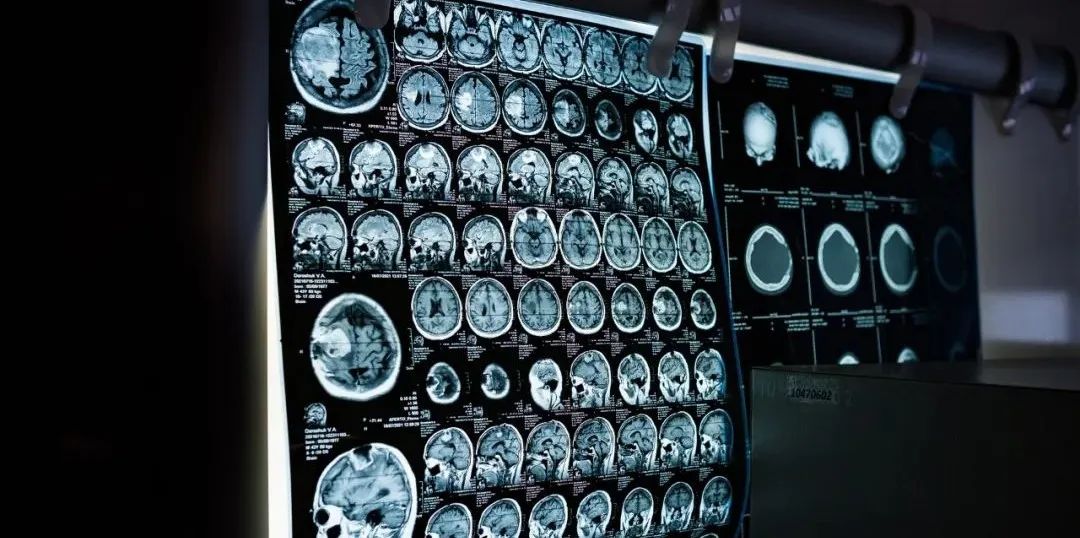

米度生物與Xing Imaging LLC在核心能力和業(yè)務(wù)范疇上,具有顯著的戰(zhàn)略協(xié)同性。通過本次收購,加強(qiáng)了東誠藥業(yè)核藥臨床影像服務(wù)能力,打造了新核藥臨床轉(zhuǎn)化網(wǎng)絡(luò),完善了公司在核醫(yī)藥領(lǐng)域的產(chǎn)業(yè)布局。同時,通過本次收購也將為公司增加新的利潤增長點,提升公司的抗風(fēng)險能力,進(jìn)一步優(yōu)化整體戰(zhàn)略的目標(biāo),實現(xiàn)公司的可持續(xù)發(fā)展。 伴隨東誠核藥圈不斷完善,在核藥創(chuàng)新研發(fā)的多年布局,從2023年開始,公司核藥研發(fā)管線將真正迎來落地期,東誠藥業(yè)也將進(jìn)入騰飛新時期。 針對本次收購,米度生物CEO吳昊偉、Xing Imaging LLC聯(lián)合創(chuàng)始人兼CEO Gilles Tamagnan博士提到: 米度生物CEO吳昊偉 Xing Imaging LLC是獨(dú)一無二的,其強(qiáng)大的PET中心網(wǎng)絡(luò)可以為行業(yè)合作伙伴提供最先進(jìn)的神經(jīng)PET成像示蹤劑,我很高興本次收購能夠提供以前在中國無法提供的全方位分子影像臨床研究服務(wù)。這是兩家公司的完美結(jié)合,我們將共同努力,從核醫(yī)學(xué)藥物研發(fā)到中國臨床研究的各個階段,加速新藥的開發(fā)。 Xing Imaging LLC聯(lián)合創(chuàng)始人兼CEO Gilles Tamagnan博士 這是一個巨大的機(jī)會,我們通過提供臨床分子影像服務(wù)作為評估新型治療藥物研究的重要組成部分,進(jìn)一步推動我們對中國患者的承諾。這次聯(lián)合代表著一個更大戰(zhàn)略的開始,我們將在中國和其他地區(qū)擴(kuò)展這些服務(wù)。 Xing Imaging LLC, 是一家注冊在美國,并在中國開展業(yè)務(wù)的臨床PET影像服務(wù)公司。目前主要的業(yè)務(wù)范圍包括,專業(yè)從事放射性示蹤劑生產(chǎn)、PET采集和分析;利用獨(dú)特的機(jī)會來滿足中國PET臨床成像研究的需要;其作為生物標(biāo)記物成像公司,為放射性藥物成像提供端到端的服務(wù)支持。Xing Imaging LLC的聯(lián)合創(chuàng)始人和公司管理層擁有平均超過25年的經(jīng)驗。 2020年7月,東誠藥業(yè)收購作為行業(yè)稀缺的核藥CRO“獨(dú)角獸企業(yè)”——米度生物,通過嫁接放射性藥物臨床轉(zhuǎn)化的斷橋,打造了獨(dú)特的藥物研發(fā)CRO平臺。針對放射性藥物,米度生物可提供從早期開發(fā)、藥學(xué)研究、臨床前研究、臨床研究及注冊申報的一站式服務(wù)。米度生物具有放射性藥物研發(fā)及申報經(jīng)驗,目前已幫助4個18F-藥物和1個99mTc-藥物獲得臨床批件,有超過10個放射性藥物正在實施過程中(18F, 68Ga,89Zr, 90Y, 99mTc,166Ho, 177Lu)。